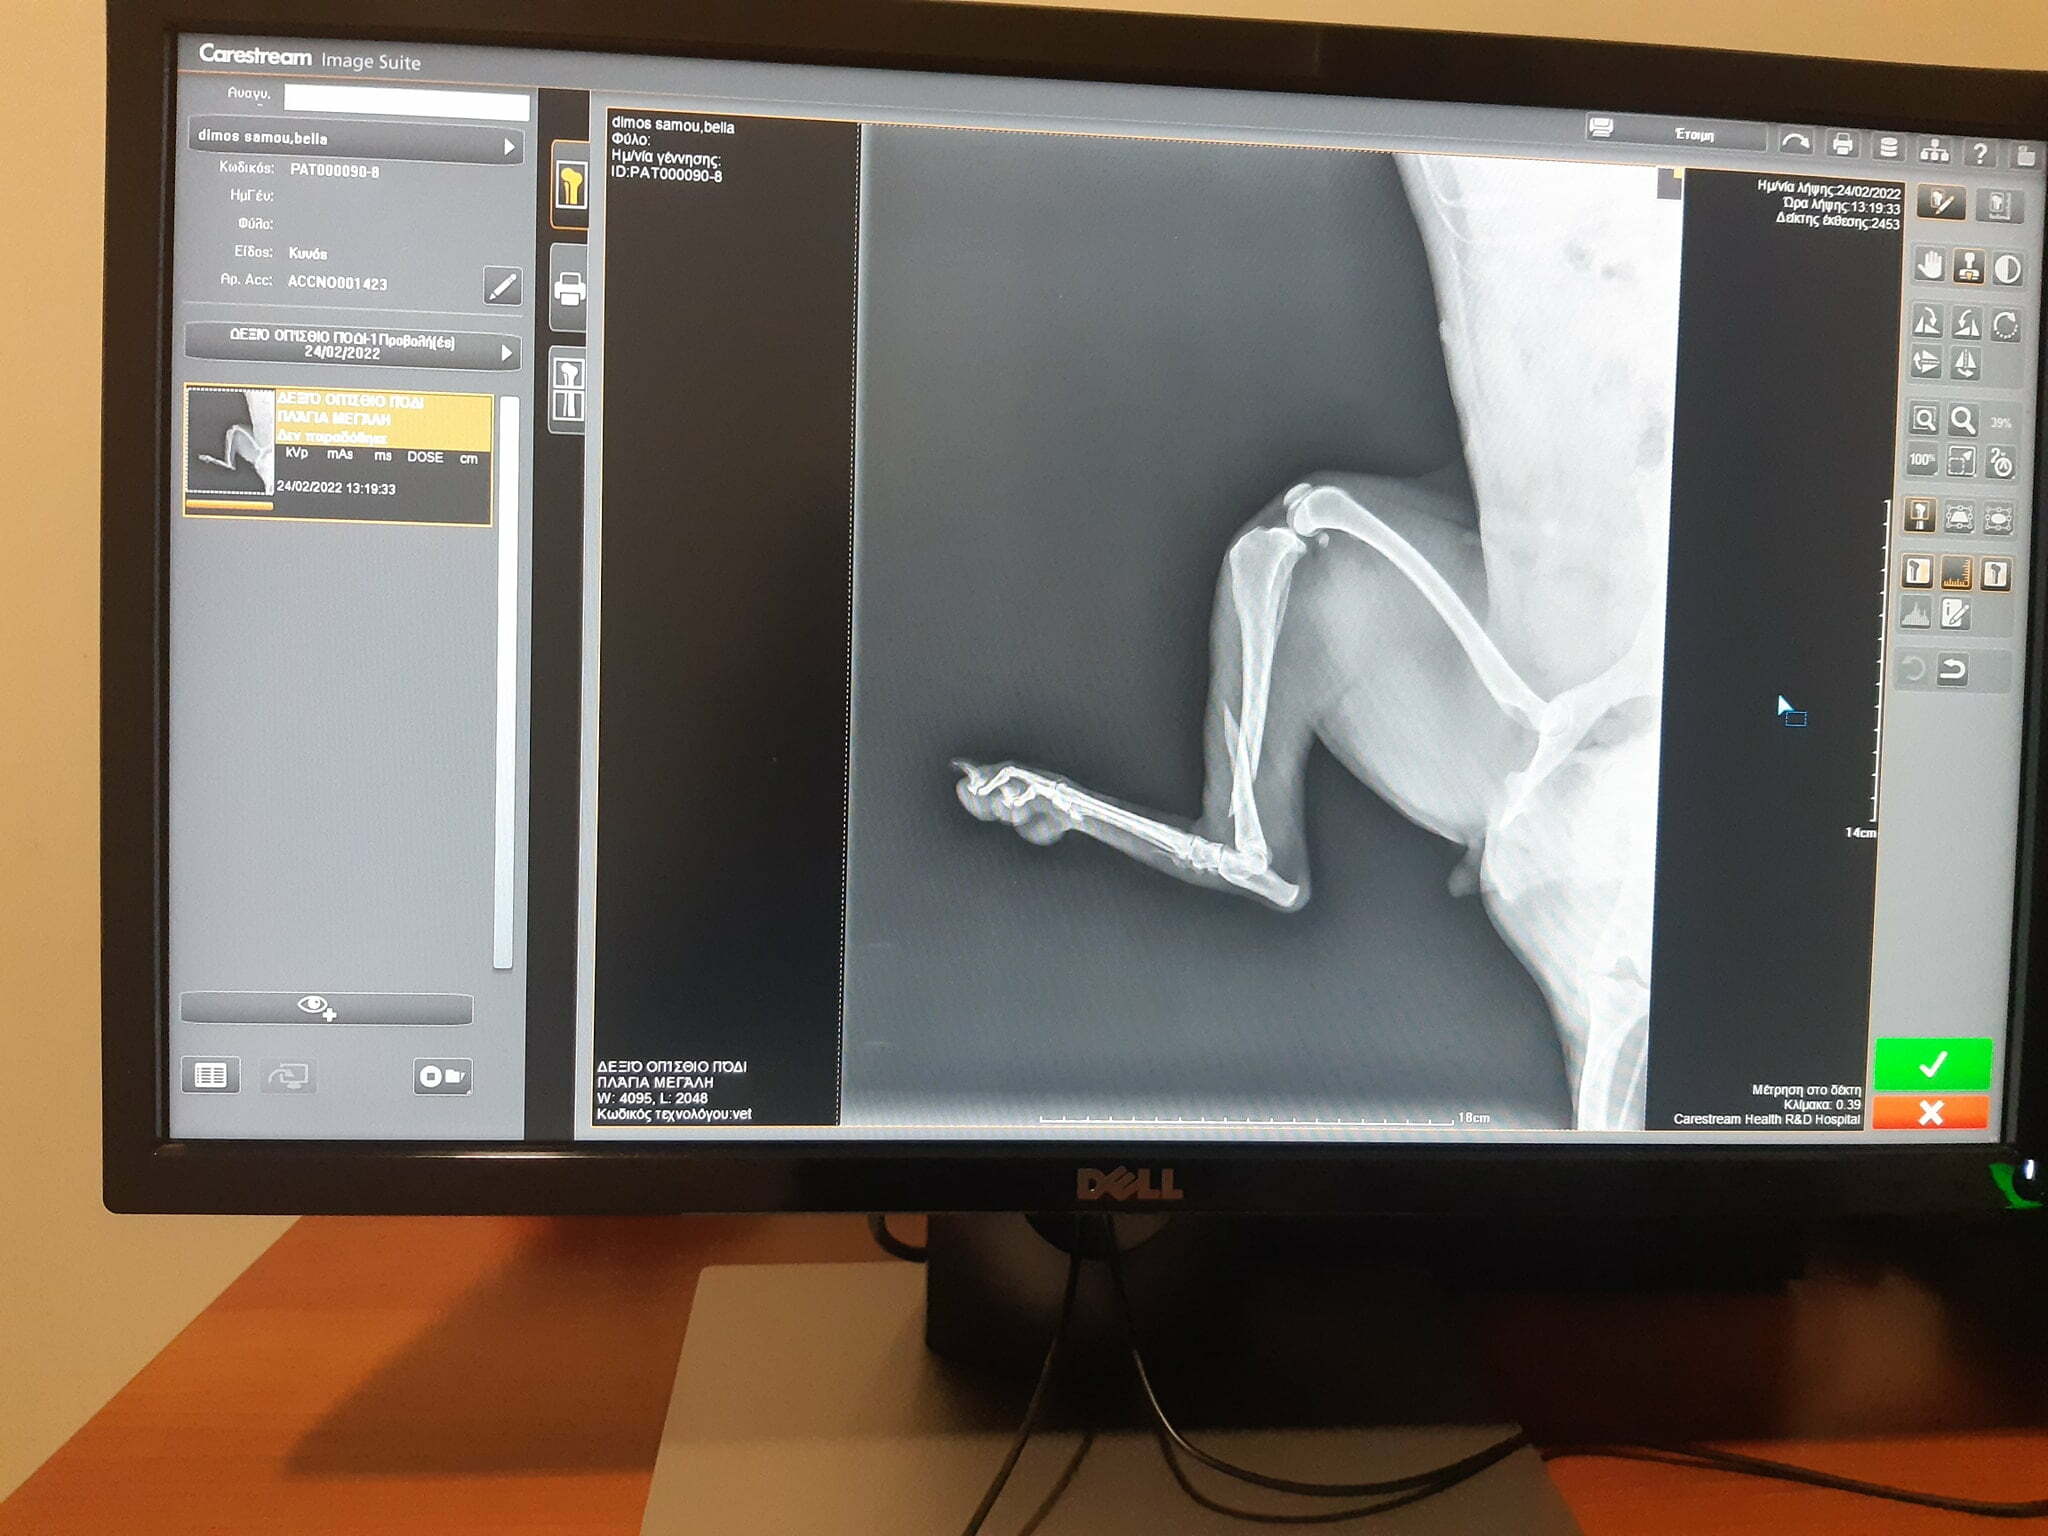

Σύσσωμη η ομάδα νεανίδων βόλεϊ του Πολυκράτη συνόδεψε σήμερα τα ξημερώματα την άτυχη Μπέλλα στο ταξίδι της στην Χίο, όπου έγινε η επέμβαση στο σπασμένο πόδι της από τους ορθοπεδικούς κτηνίατρους.